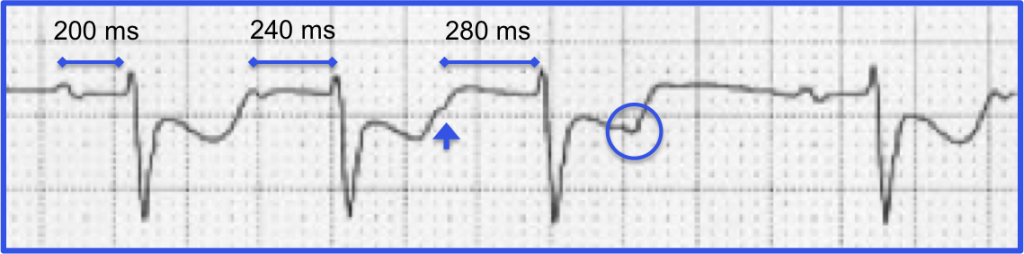

Now the heart rhythm is second degree AV block type 1 (Wenckebach).

How can you tell? In the first place we see clustering of QRS complexes (huge tip-off) and we already know that AV conduction is precarious. The initial cardiac cycle of each cluster shows a constant PR-interval.

When we take a closer look at the rhythm strip we see progressive prolongation of the PR-interval until a P-wave is “dropped” proving that the heart rhythm is second degree AV block type 1 (Wenckebach).